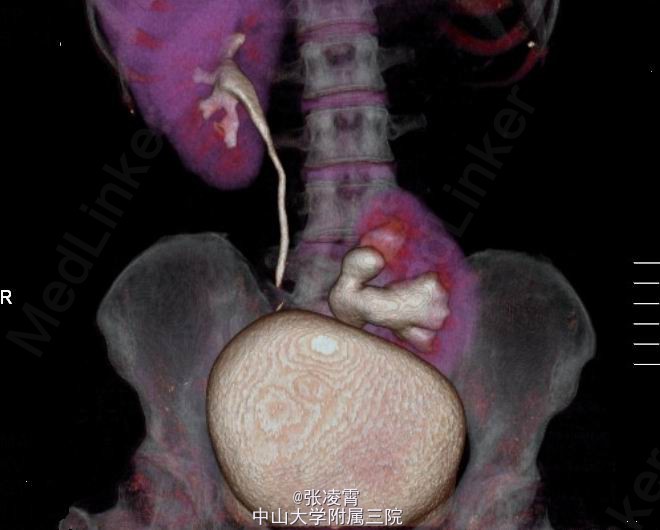

体格检查:体温37.2oC,心率82次/min,呼吸19次/min,血压110/80,皮肤黏膜、巩膜无黄染,全身浅表淋巴结无肿大,心肺未见异常,双肾区无红肿、隆起,左下腹可扪及一边缘清楚的实性包块,呈椭圆形,大小约13x8cm,压痛(+),反跳痛(-)。左肾区叩击痛(-),左肾肋脊点,肋腰点压痛(-),右侧肋脊点、肋腰点压痛(-)。腹平软,左侧输尿管走行区压痛(-),右侧输尿管走行区压痛(-),膀胱区无膨隆,压痛阴性,双侧腹股沟区未触及肿物。 实验室检查:血、大便常规,血生化,胸片,心电图均无明显异常。尿常规:血细胞(++),白细胞(++)尿沉渣白细胞计数252个/μl。 影像学检查:双肾、盆腔螺旋CT平扫+增强扫描+计算机四维成像提示:左肾位于腰4~骶2椎体水平,左肾盂交界处可见一大小约21x18mm高密度结节,边界锐利,左肾盂、肾盏扩张,4条左肾动脉分别起自腹主动脉、右侧髂总动脉及左侧髂内动脉,左肾静脉汇入右肾静脉。左输尿管较对侧短,无明显扩张,双肾形态、大小正常,肾实质未见异常密度影,增强扫描未见强化。右肾盂、肾盏、输尿管无明显扩张,膀胱充盈良好,壁光滑,腔内未见异常充盈缺损。